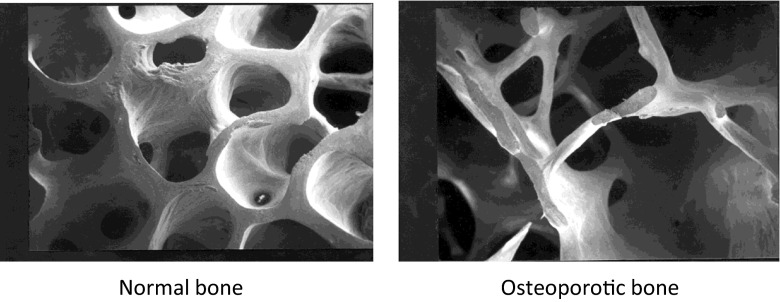

#健康出行节# #【闪光时刻】主题征文第二期#目前骨质疏松症严重影响你的健康,而且10个人中有9个人都在服用药物防治骨质疏松症,你服用的药物到底有没有用呢?一年打一针抗骨质疏松的神药唑来膦酸, 你想知道的相关问题解答 说法众说纷纭,而物理康复运动是预防和治疗骨质疏松症的重要刺激因素,证据明确,而且还绿色有效、经济方便,对各类人群都有效,方便你的出行,让你的出行更健康。